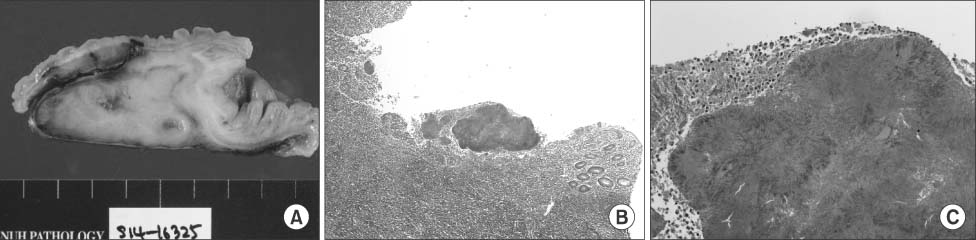

Gross pathology revealed severe inflammation and adhesion between the appendix and the adjacent appendiceal serosal surface. Irregular nodularity was seen in the distal portion of the ileal mucosal area, while intraluminal obliteration was found due to the severe inflammation (Fig. 3A).

Light microscopic examination revealed acute suppurative appendicitis with a periappendiceal abscess and actinomycotic colonies. At higher magnification, a typical sulfur granule surrounded by neutrophils was found that was confirmed as appendiceal actinomycosis (Fig. 3B, C).

Fig. 3

(A) Gross appearance of the excised specimen. (B) Pathological examination: Presence of Actinomyces israelii. Acute suppurative appendicitis with a periappendiceal abscess and actinomycotic colonies characterized by sulfur granules (H&E stain, ×40). (C) Pathological examination: Presence of A. israelii. Acute suppurative appendicitis with a periappendiceal abscess and actinomycotic colonies characterized by sulfur granules (H&E stain, ×200).